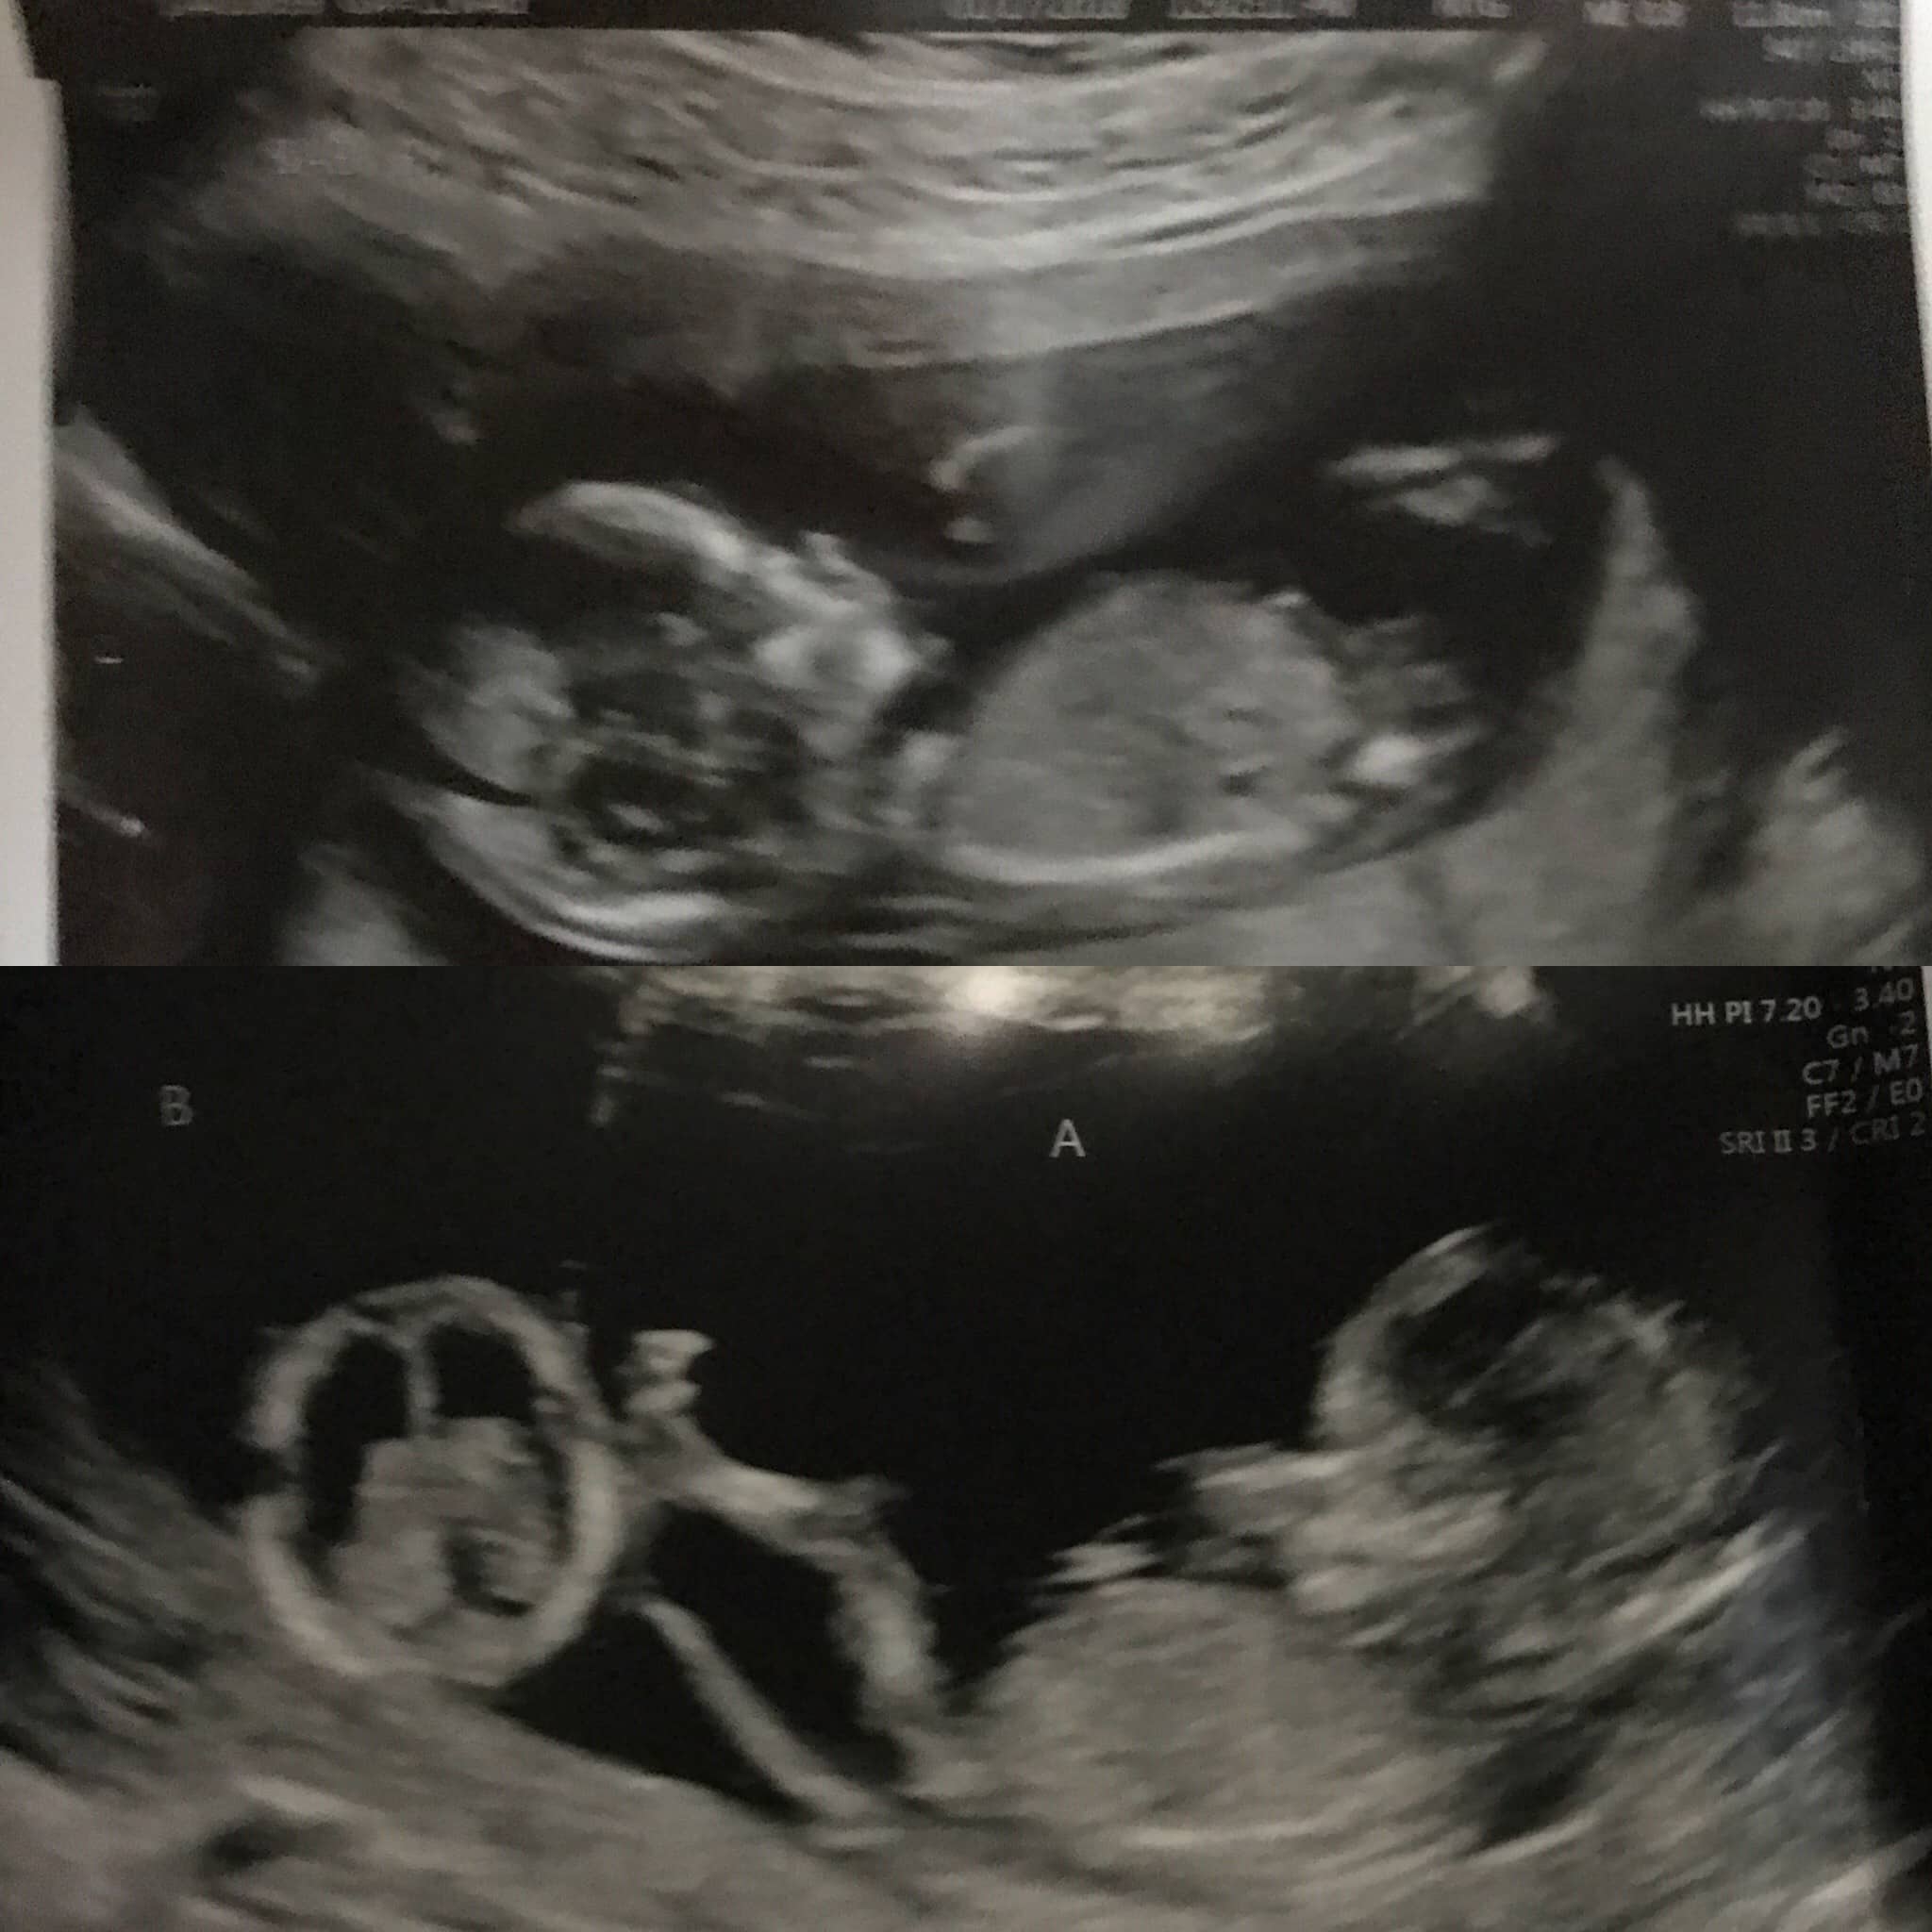

Ultrasound Photos at 14 Weeks Pregnant With Twins